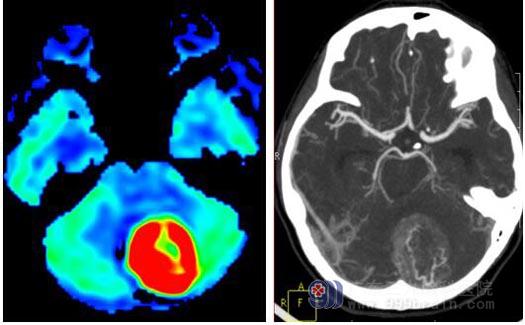

女,18岁,患者约1年前无明显诱因出现间断头痛,加重1月,到外省某三甲医院就诊,行颅脑MRI+MRV检查示:左侧小脑半球占位性病变,压迫左侧乙状窦和直窦,考虑脑膜瘤可能性大。今患者来我院就诊,行头颅CTA及MRS、ASL检查(见图1、2,MRS图未能给出)。头颅CTA检查示左侧小脑幕占位性病变血供丰富,病变紧贴窦汇和直窦,建议补充MR+MRS检查,脑膜瘤待排。ASL序列呈高灌注改变,MRS+ASL序列提示Cho峰明显升高,NAA峰基本消失,支持脑膜瘤表现,待排血管周细胞瘤。后于我院行左侧小脑幕窦旁占位病变切除术+右侧脑室钻孔外引流术,术后病理示左侧小脑幕下及窦旁血管周细胞瘤 WHO II级。

图1-2,ASL、CTA、MRS,ASL示病变明显高灌注,CTA示病灶内多发迂曲增粗血管影。